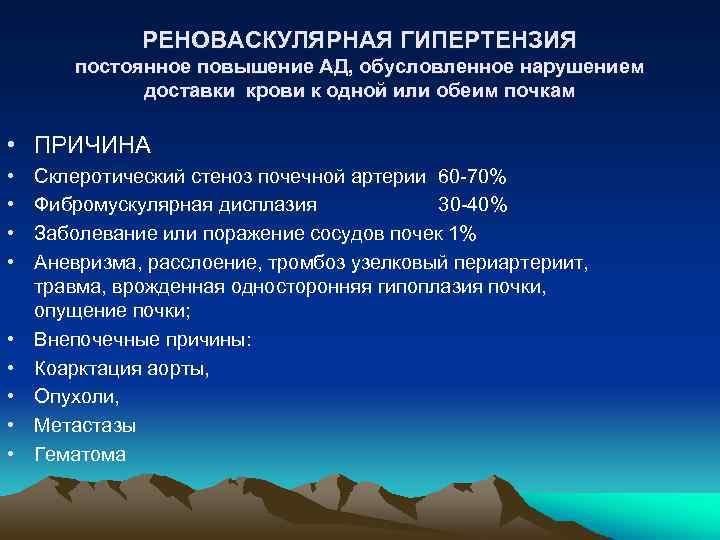

РЕНОВАСКУЛЯРНАЯ ГИПЕРТЕНЗИЯ постоянное повышение АД, обусловленное нарушением доставки крови к одной или обеим почкам • ПРИЧИНА • • • Склеротический стеноз почечной артерии 60 -70% Фибромускулярная дисплазия 30 -40% Заболевание или поражение сосудов почек 1% Аневризма, расслоение, тромбоз узелковый периартериит, травма, врожденная односторонняя гипоплазия почки, опущение почки; Внепочечные причины: Коарктация аорты, Опухоли, Метастазы Гематома

РЕНОВАСКУЛЯРНАЯ ГИПЕРТЕНЗИЯ постоянное повышение АД, обусловленное нарушением доставки крови к одной или обеим почкам • ПРИЧИНА • • • Склеротический стеноз почечной артерии 60 -70% Фибромускулярная дисплазия 30 -40% Заболевание или поражение сосудов почек 1% Аневризма, расслоение, тромбоз узелковый периартериит, травма, врожденная односторонняя гипоплазия почки, опущение почки; Внепочечные причины: Коарктация аорты, Опухоли, Метастазы Гематома